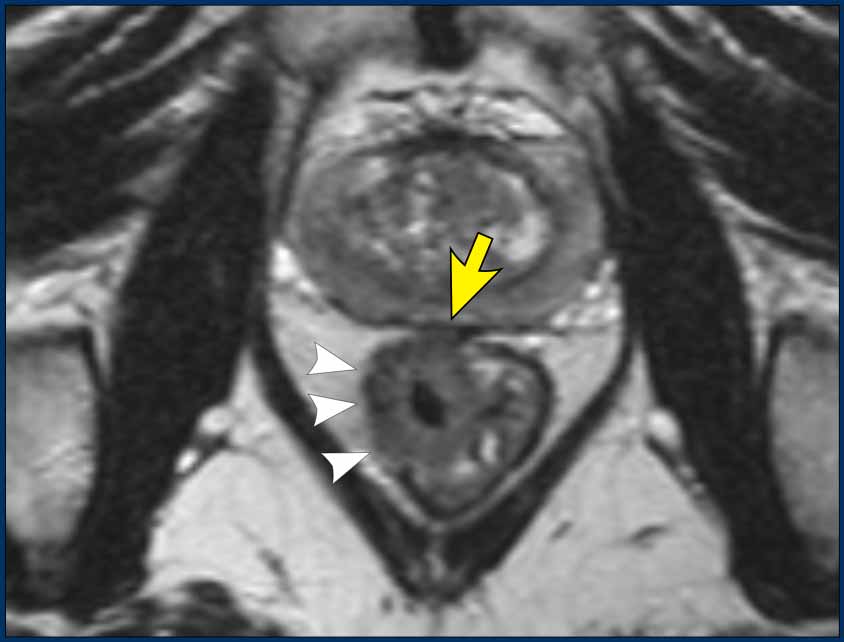

T3 Tumors

T3 tumors extend beyond the muscularis propria into the mesorectal fat.

MRI findings:

• Interruption of the hypointense muscularis propria

• Spicular or nodular tumor signal extension into the mesorectal fat

Image

This partly annular tumor (8–12 o’clock) invades the perirectal fat, with an anterior MRF margin <1 mm (arrow), consistent with cT3ab MRF+.

• Intact muscularis propria is visible from 12 to 8 o’clock

• Right-sided interruption of the muscularis, with nodular tumor extension into the perirectal fat (arrowheads)